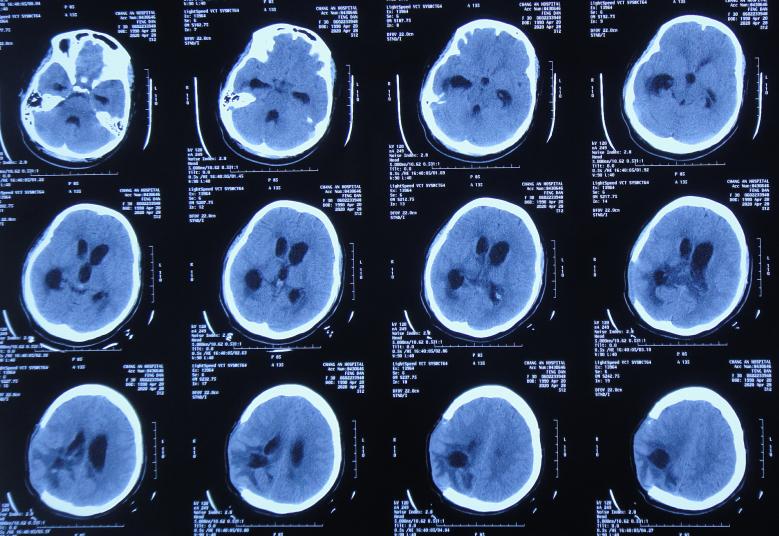

开颅术后15天即2020年4月17日(腰大池引流术后7天),查头颅CT示仍脑膨出( 图-4 ),因腰大池引流管堵塞,给予拔除并第2次重新置换腰大池。

图-4: 2020年4月17日头颅CT

开颅术后26天2020年4月28日(腰大池引流管第4次脱出后5天),复查头颅CT发现幕上脑室系统扩张( 图-5 );但因患者症状好转,可在搀扶下独立行走,未予处理。

图-5: 2020年4月28日头颅CT